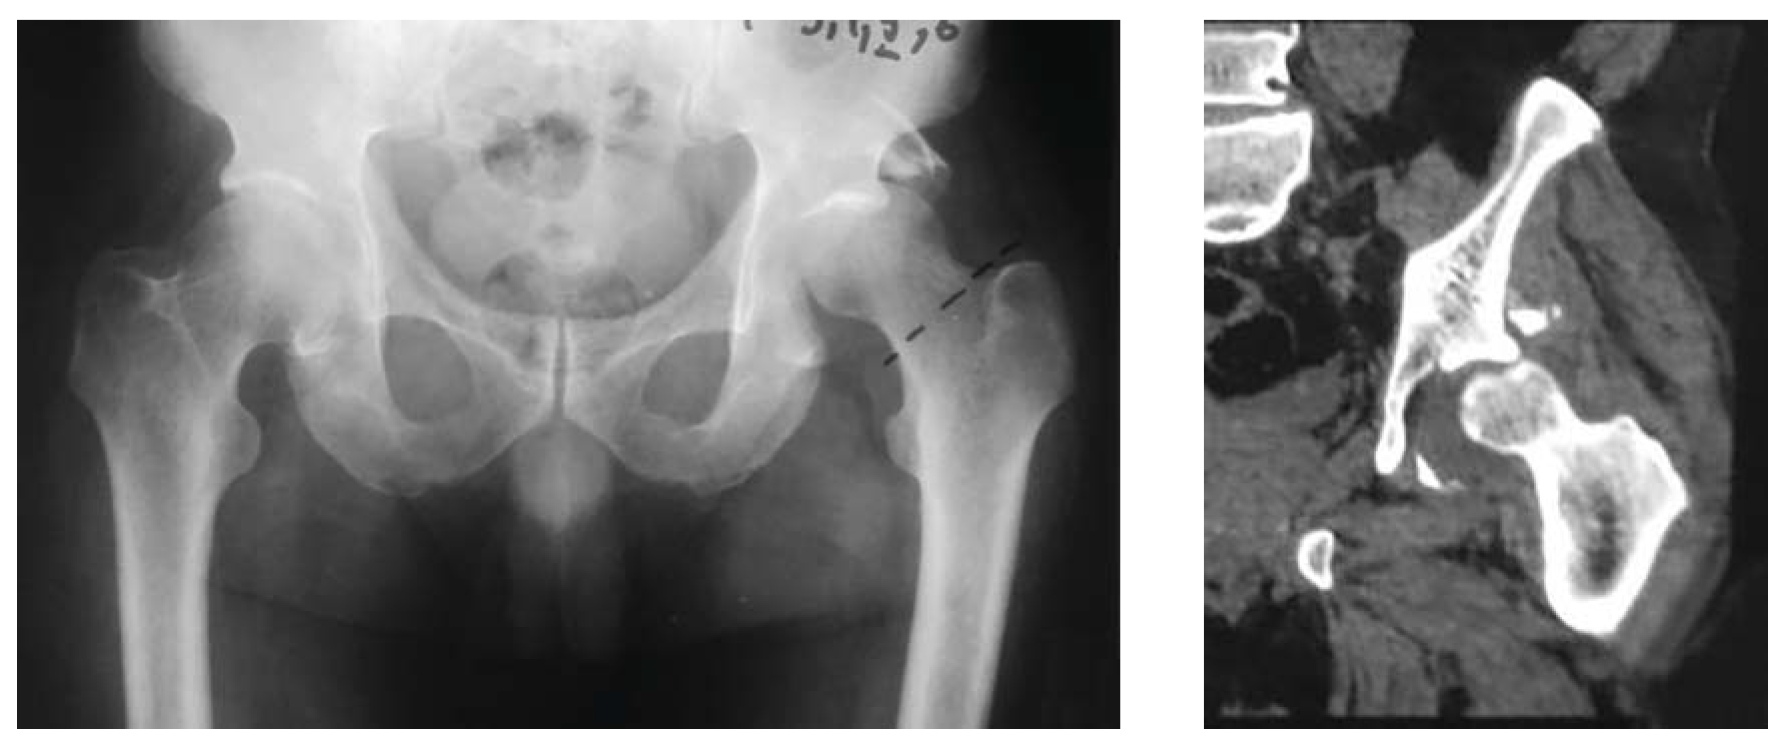

В следующем клиническом примере на рентгенограмме таза в переднезадней проекции мы определяем целостность 4 основных референтных линий: подвздошно-гребешковая, подвздошно-седалищная, контуры запирательного отверстия, задняя стенка (рис. 2, а). На первом этапе диагностики мы исключили все возможные 10 типов по классификации Judet—Letournel, однако на рентгенограмме определяется центральное смещение головки бедренной кости и наличие отломков вне контуров референтных линий (рис. 2, б).

Обращает на себя внимание разрушение фигуры слезы. Анатомически это объясняется локализацией повреждения в передненижних отделах вертлужной впадины. Соответственно, хорошо различимые смещенные костные отломки представляют собой часть четырехсторонней пластинки, которая является дном вертлужной впадины (рис. 2, в).

Выполнение прицельных рентгенограмм позволяет нам подтвердить целостность анатомических структур, формирующих референтные линии (передняя и задняя колонны, края впадины). Наличие центрального вывиха головки бедренной кости характерно для переломов с поперечной линией излома, когда головка бедренной кости вклинивается между подвздошной костью и лобково-седалищным сегментом. В данном случае на рентгенограммах в подвздошной и запирательной проекции отчетливо определяется протрузия головки бедра в таз в проекции четырехсторонней пластинки, что подтверждает перелом дна вертлужной впадины (рис. 2, д).

Следует отметить, что повреждение четырехсторонней пластинки характерно для переломов на фоне остеопороза.

Рис. 2.а — обзорная рентгенография таза при поступлении; б — первый этап определения атипичного перелома четырехсторонней пластинки; в — окончательное определение атипичного перелома четырехсторонней пластинки; г, д — детализация перелома четырехсторонней пластинки с помощью прицельных рентгенограмм в запирательной и подвздошной проекции.